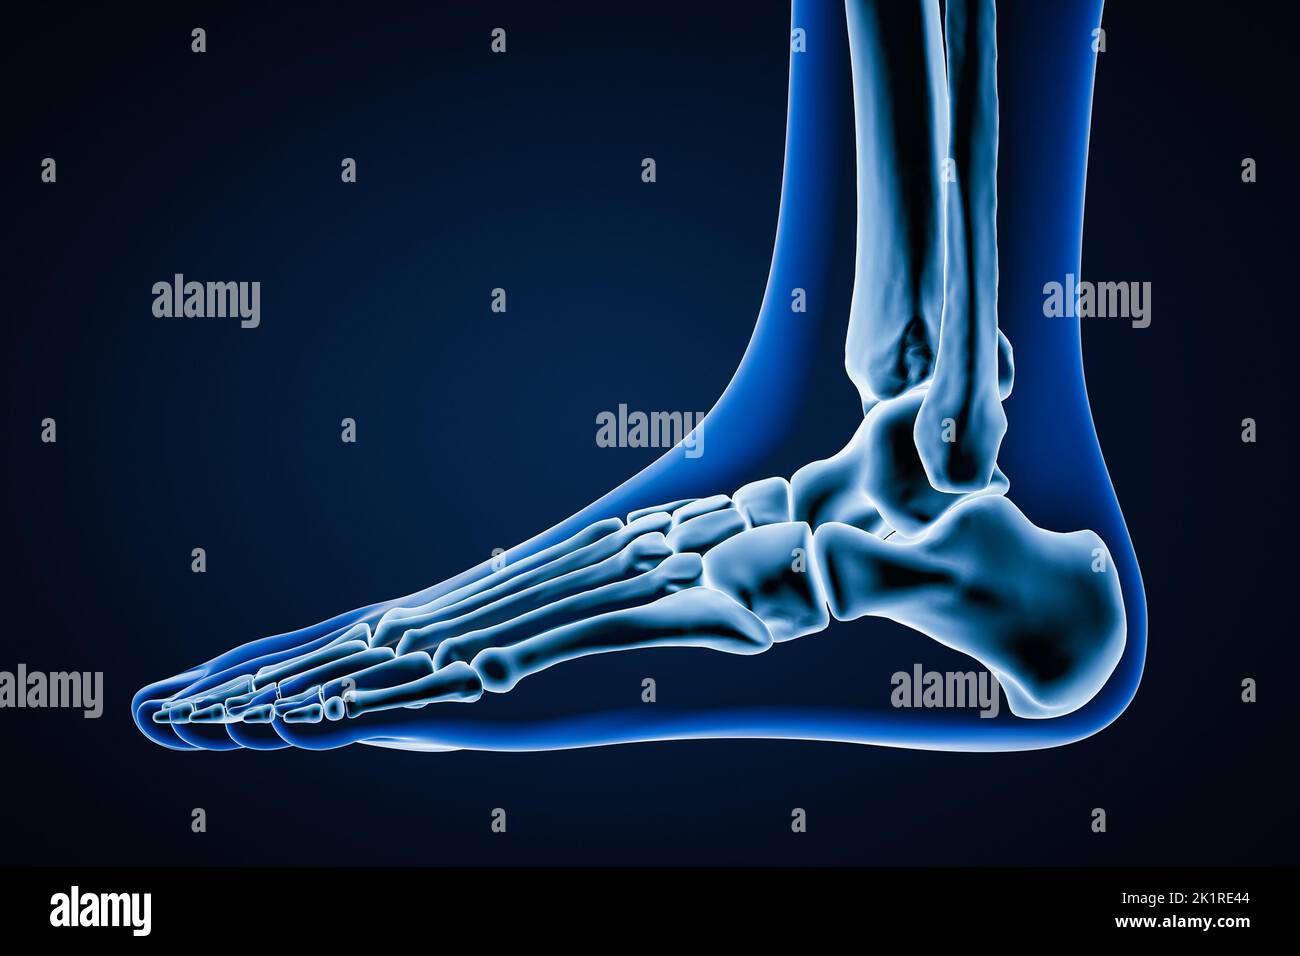

RF2K1RE44–Vue latérale ou en profil d'os précis du pied gauche humain avec contours du corps sur fond bleu 3D illustration de rendu. Anatomie, ostéologie, ortho